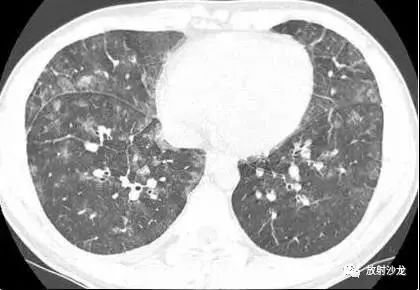

一名21岁男因发热咳嗽一周就诊。影像学结果检查如下:

胸部CT(图1-3)显示,支气管壁增厚,小叶中央型结节,磨玻璃影或小叶实变,轴向间质和小叶间隔增厚,以及双侧少量胸腔积液。胸片(图4)显示弥漫性斑片状或结节状磨玻璃影,线性阴影,以及双侧少量胸腔积液。

最终诊断:肺炎支原体肺炎

X线片上最常见的表现是高密度影,节段性或非节段性分布。CT上,最常见的是支气管壁增厚(81%),其次是小叶中央型结节(78%),磨玻璃影(78%)和小叶实变(61%)。轴向间质及小叶间隔增厚常见。胸片中通常很难鉴别肺炎,但在高分辨CT中可见。其它表现是胸腔积液和淋巴结肿大。成人CT中常表现为细菌性支气管肺炎和病毒性间质性肺炎的合并感染。但儿童肺炎支原体肺炎与细菌性大叶性肺炎相似。